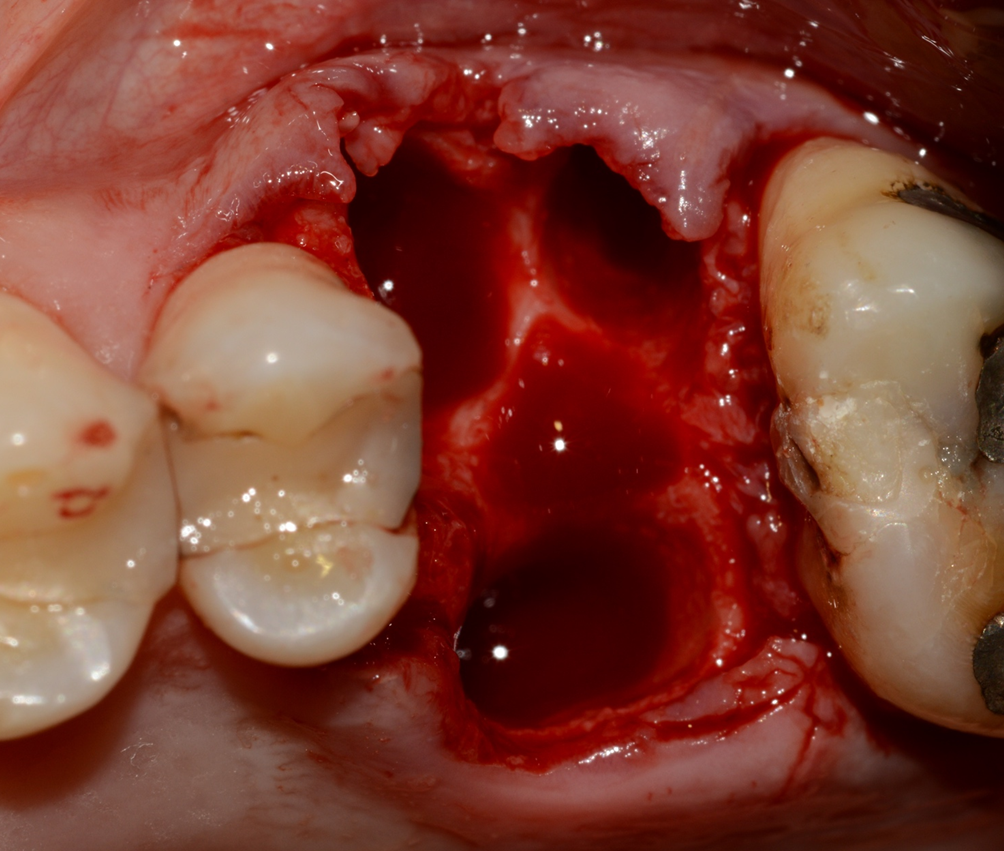

Existem várias razões pelas quais um dente pode vir a ser condenado à exodontia. Em nossa rotina clínica, as infiltrações de cáries sob restaurações extensas e as fraturas radiculares (ou corono-radiculares) estão entre as mais presentes. Nesses casos, normalmente o osso circundante ainda se apresenta em boas condições para receber um implante, direcionando a indicação de tratamento para exodontia e implante imediato. Sempre que for possível realizar essa abordagem, será extremamente vantajoso ao paciente, pois o número de procedimentos cirúrgicos será reduzido, assim como o tempo total de tratamento.

Todavia, em alguns casos, não há remanescente ósseo suficiente para a instalação segura de um implante. Nestas situações, o que nunca se deve fazer é apenas extrair o dente e deixar que a cicatrização ocorra através do preenchimento do alvéolo com sangue e subsequente neoformação óssea. Essa abordagem pode gerar sequelas, tais como a reabsorção aumentada do tecido ósseo, e por consequência, dificultar a instalação de um implante no futuro.

A sequência de imagens a seguir apresenta casos da aplicação clínica do Extra Graft em cirurgias de exodontia e implante imediato com preenchimento dos gaps, e apenas exodontia e preenchimento alveolar para favorecer a regeneração óssea.